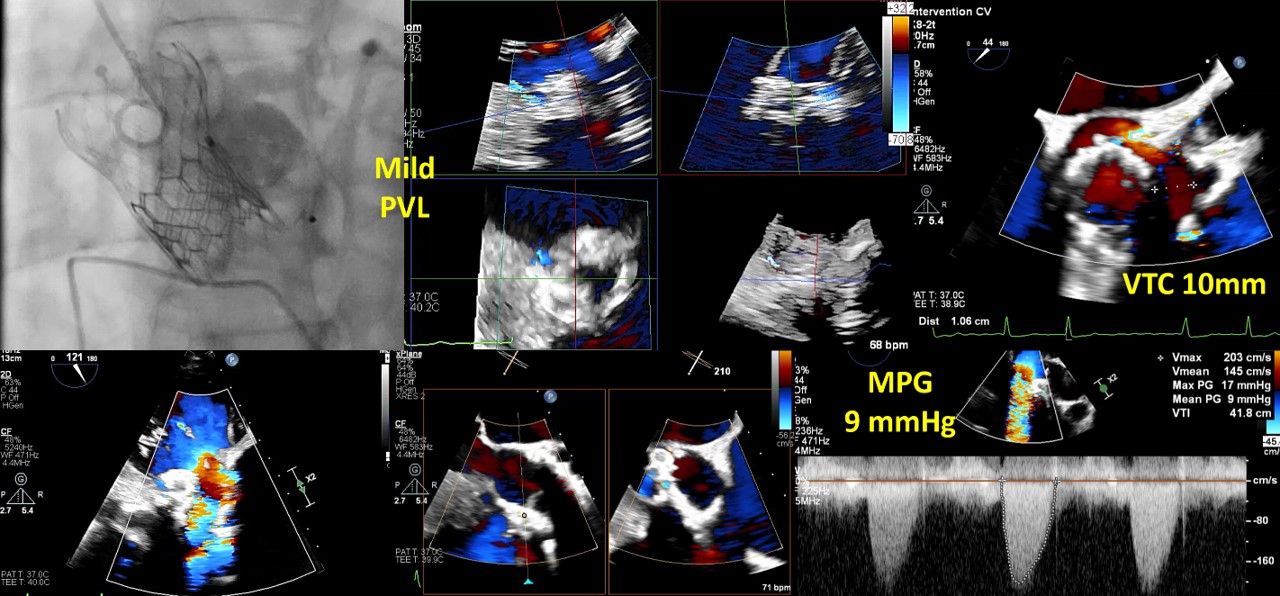

Transesophageal echocardiography revealed severe aortic regurgitation due to THV leaflet perforation following untreated infective endocarditis, along with a preexisting paravalvular leak caused by the calcified raphe of the type 1 bicuspid aortic valve.Given the patient’s deteriorating clinical status despite inotropic support, and after three negative blood cultures and five weeks of antibiotic treatment, the heart team decided to proceed with transcatheter treatment.

A combined procedure including transcatheter closure of paravalvular leak and redo-TAVR, was performed under general anesthesia with transesophageal echocardiographic guidance.1. Bilateral approach via left femoral artery(8Fr non-kinking sheath), right femoral artery(16Fr E-sheath).2. We used a Terumo guide wire accompanied with AL/5F diagnostic catheter to cross the defect of paravalvular leak.3. MP/7F guide catheter accompanied with 6 x 40mm Mustang balloon crossed the paravalvular leak defect by using balloon assisted tracking technique.4. Wire exchanged to Confida super-stiff wire.5. Amplatzer Vascular Plug II 9-12mm occluder was deployed successfully under TEE guidance. 6. TEE showed paravalvular leak downgrade to mild. There was no nearby structure damage, no new pericardial effusion, nor coronary obstruction.7. An Extra-small Safari super-stiff wire was placed in the left ventricle.8. A 23mm Sapien 3 valve was deployed successfully with 1cc overfill.9. The paravalvular leak and valvular AR both sealed successfully, with only minimal paravalvular leak remain.10. The transvalvular mean pressure gradient was 9mmHg, and the valve functioned well.

This case report highlights a successful percutaneous closure of a paravalvular leak using an Amplatzer Vascular Plug, followed by a TAVR-in-TAVR intervention in the same procedure. This approach effectively managed a severe THV failure induced by infective endocarditis, which was complicated by severe valvular regurgitation and a paravalvular leak with hemodynamic instability.